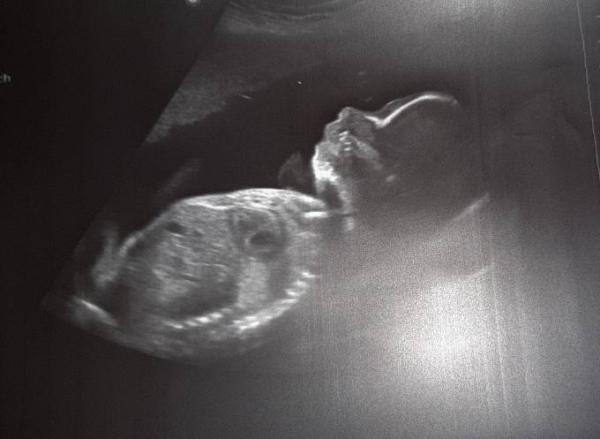

Huhu, ich hatte heute meinen nächsten Termin. Der Eisenwert ist von 11,1 vor 4 Wochen wieder auf 13,9 gestiegen. Das Mittel habe ich nach 2 Tagen gegen Hohes C Plus Eisen ausgetauscht. Scheint geholfen zu haben. Die Maus ist mittlerweile 30 cm groß und 600 gr schwer. Er ist super zufrieden, aber mein Gebärmutterhals ist seit den letzten 4 Wochen schon 1 cm kürzer geworden. Also nix mit Übungswehen. Muss jetzt ins Krankenhaus, um zu gucken, wie es weitergeht. Magnesium hab ich heute auf der Arbeit von einer Pharmarefferentib geschenkt bekommen, das kommt jetzt zum Einsatz. Da es schon Kind Nr. 6 ist, geht halt alles was schneller. Aber bis kurz nach Weihnachten sollte die Maus schon drin bleiben. Zum Glück tut es mir nicht immer weh, sondern nur, wenn ich Stress habe. Zum Glück bin ich relativ stressresitent. Ich denke eher, die Verkürzung kommt vom Husten, der jetzt immerhin schon 7Wochen anhält. Ich hoffe, es geht euch gut

Bild zu Der nächste Termin - Forum für Januar - Mamis